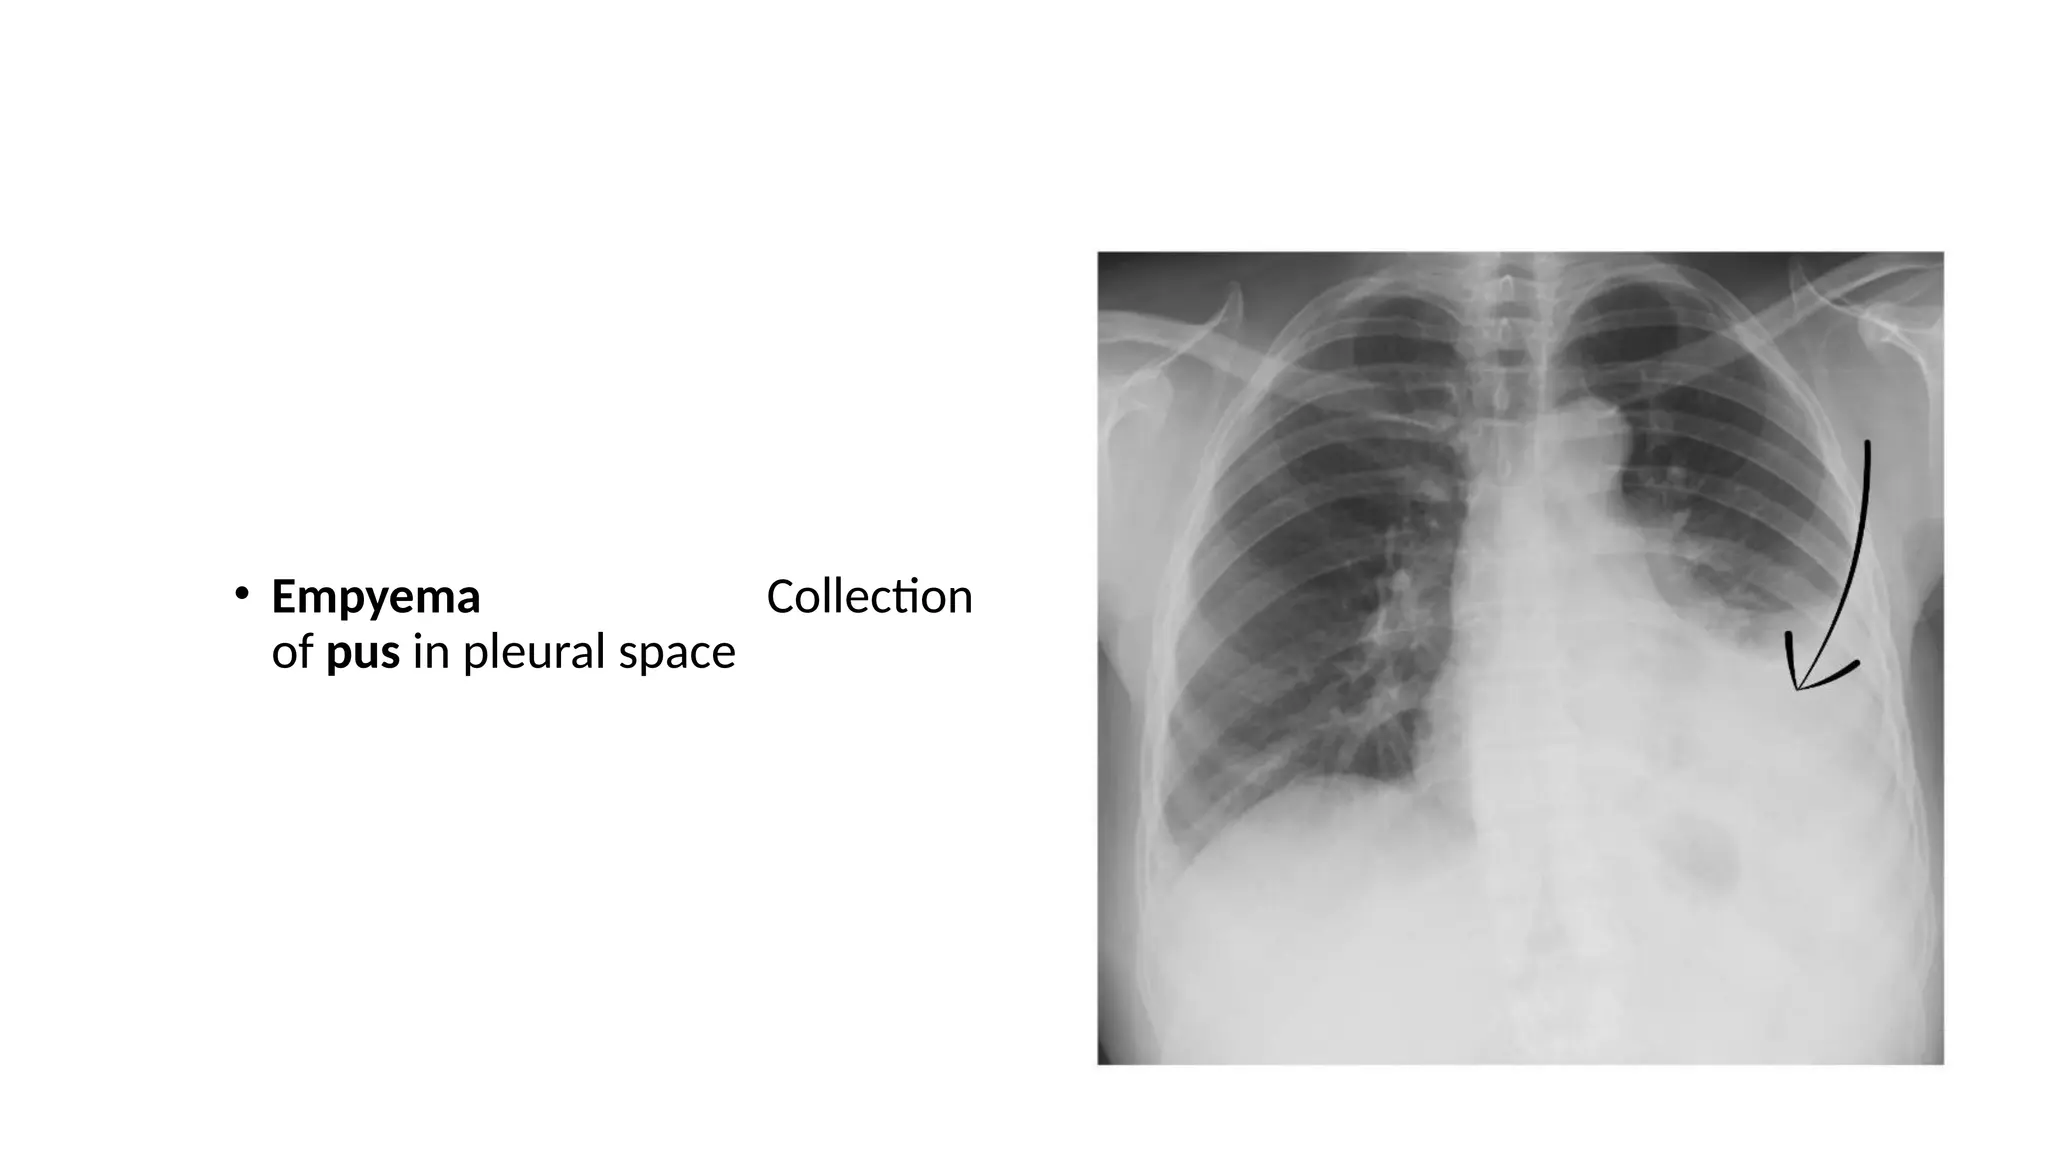

• Empyema Collection

of pus in pleural space

• Empyema Collection ofpus in pleural space

• 43.